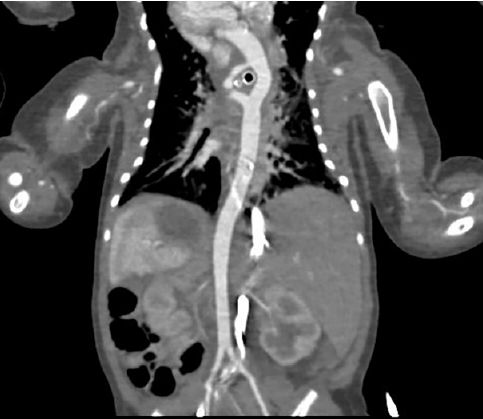

Se realizó videolaringoscopia (Video) con fibra óptica, ecocardiografía y angiografía por tomografía computarizada (TC) de tórax (Figs. 1 y 2).

Figura 1.- Tomografía computarizada con contraste, sección coronal

La TC con contraste mostró el doble arco aórtico rodeando la tráquea (Figura 5).

Figure 5.- Imagen de corte coronal de tomografía computarizada con contraste que muestra el arco aórtico doble (líneas azules) rodeando la tráquea (círculo negro, línea amarilla).